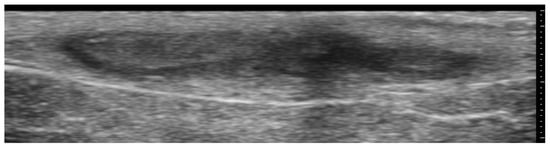

2. Infections

3. Inflammatory Dermatoses

4. Metabolic and Genetic Disorders

5. Specific Cutaneous Structure and Sites of Skin Disorders

6. Vascular Disorders

7. External-Agent-Associated Disorders

8. Neoplastic Diseases

9. Aesthetic Medicine